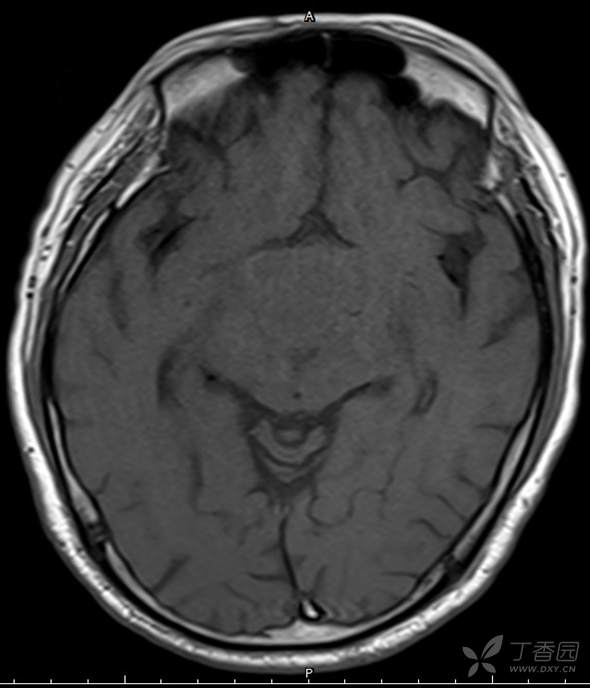

男,44岁,记忆力下降、乏力5月余,多尿3月余,CTMR全,疑难病例,能正确诊断吗?

图像不多,能诊断正确吗?有特征性吗?

T1WI